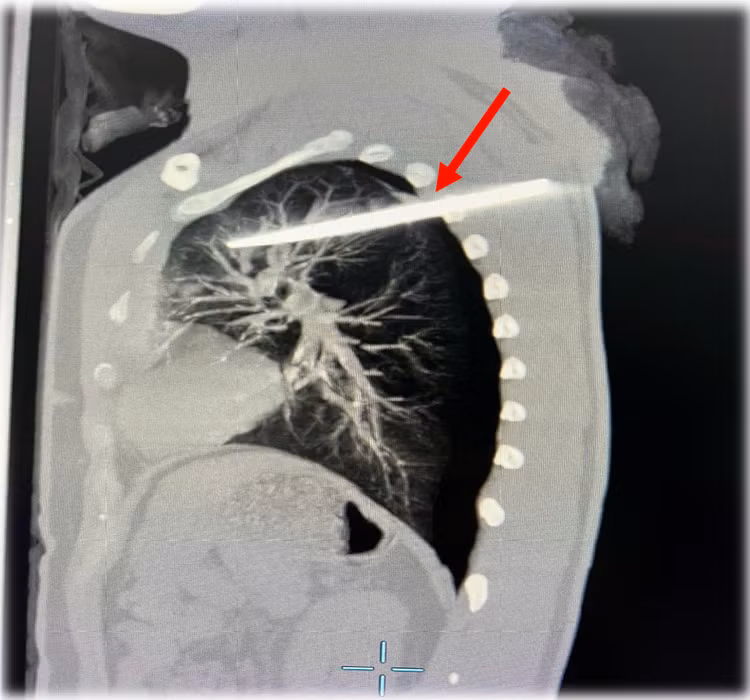

Qua chụp cắt lớp vi tính lồng ngực, các bác sĩ xác định: dị vật kim khí xuyên thấu cơ vùng lưng qua khoang gian sườn 3-4 vào nhu mô thùy trên phổi trái, xuất huyết phế nang xung quanh, tràn khí - tràn máu khoang màng phổi.

| Hình ảnh chụp cắt lớp của bệnh nhân LVD ngày 29/12/2024 tại Bệnh viện TWQĐ 108 với dị vật kim khí xuyên thấu ngực (mũi tên màu đỏ) - Ảnh BVCC |